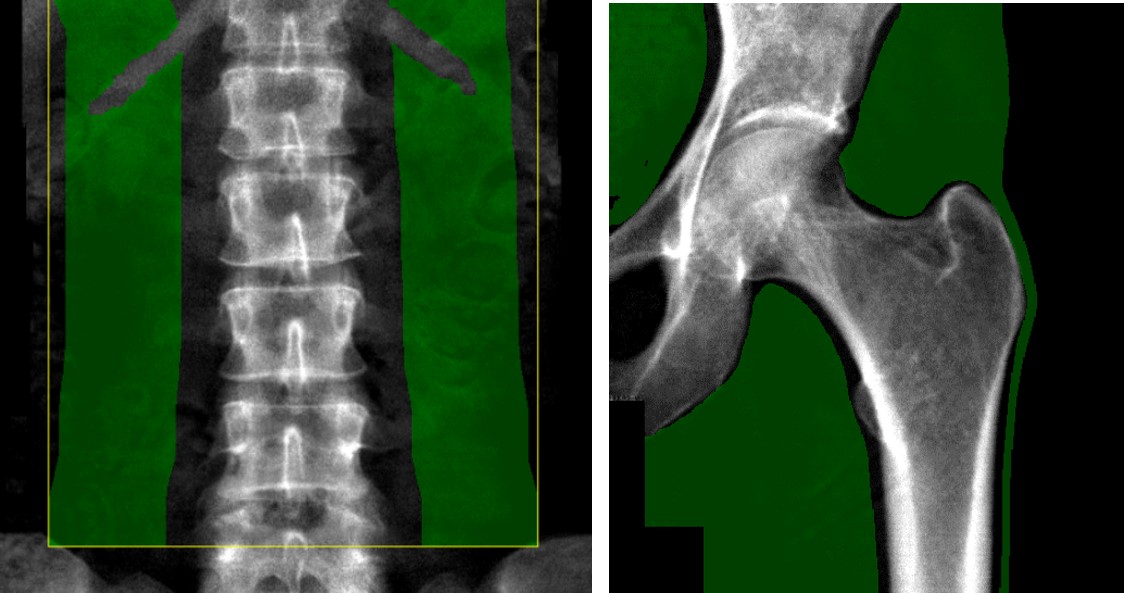

① 軟部組織領域の設定が適切であるか?

軟部組織領域とは、骨密度値を算出する際に補正に使用する軟部組織の基本データであり、この領域のX線吸収量を基準(ベースライン)として、骨量を算出します。測定部位により、適切な軟部組織領域は異なり腰椎では、椎体の両外側の軟部組織で横突起部を外した領域、大腿骨では主に頚部上部、および下部となります。軟部組織領域は小さすぎると、正確な計測ができませんので、十分に確保することが重要です(図7)。しかし、広範囲まで測定領域を広げると、腰椎では肺野が含まれ、下方では仙骨が含まれると軟部組織領域の設定に影響が出るので注意を要します。適切に測定領域を決定することが必要です。

ClinicalTips03_08.jpg

図7. 適切な軟部組織領域